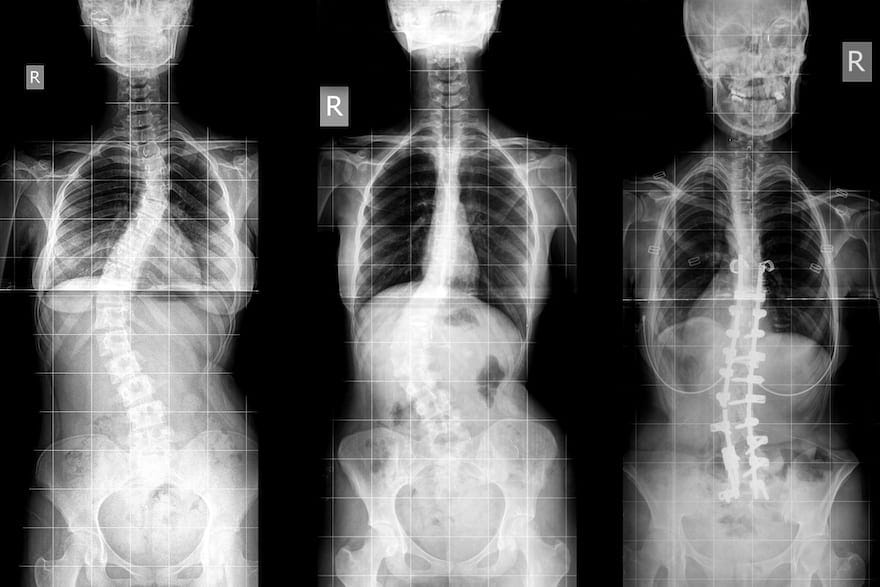

[post_page_title]Scoliosis[/post_page_title]

Lily was suffering from scoliosis, a medical condition affecting a person’s spine. Causing the spine to curve in an “S” or “C” shape, it can restrict a person’s movement.

Scoliosis mostly affects people from the ages of 10 to 20 and is more prominent in girls than boys. The problem with the condition is that it takes effect while a person is growing, which can often result in the curve getting sharper and sharper. Like a tree with a curved trunk, the taller it grows, the more noticeable the trunk becomes.